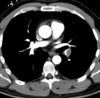

TC en TEP

Es diagnóstica, nos permite ver el trombo

95

TEP

96

4 = trombo